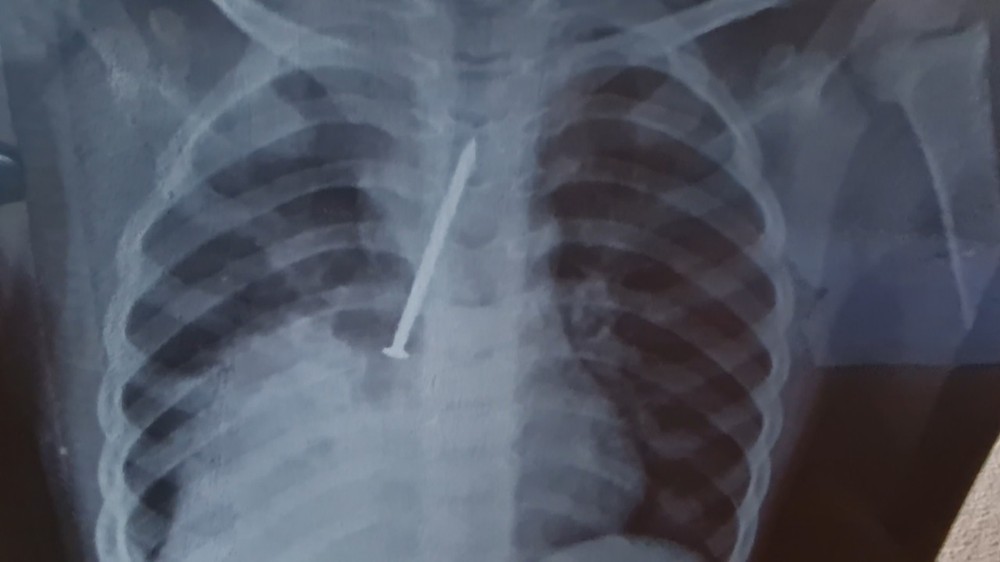

Os pais do garoto acusam o hospital de negligência, porque em nenhuma das vezes que o garoto esteve no hospital, a unidade fez um raio-x no pequeno. A família, que é de trabalhadores rurais, precisou pagar por um exame particular, onde foi identificada a gravidade do problema da criança.

Com o exame em mãos, os pais de Cauan retornaram com ele ao hospital na última segunda-feira (27), para que o menino fosse regulado. A criança foi transferida para o Hospital Geral do Estado (HGE), em Salvador, passou por cirurgia, mas morreu na sexta (1°).

No laudo médico, além da broncopneumonia, também foi identificado que Cauan teve os dois pulmões perfurados.

A profissional receitou medicamentos, passou uma nebulização e liberou a criança para voltar para casa. Com o agravamento das dores do filho, Clarice e Cosme fizeram um exame de raio x particular, no qual foi identificada a gravidade do problema do filho. A família, então, retornou com o garoto para o hospital.

Já no Hospital Geral do Estado (HGE), o garoto passou por uma cirurgia para retirar o prego. Os médicos identificaram que o material havia perfurado os dois pulmões de Cauan, que chegou a ficar internado dois dias na Unidade de Terapia Intensiva (UTI) antes de morrer.